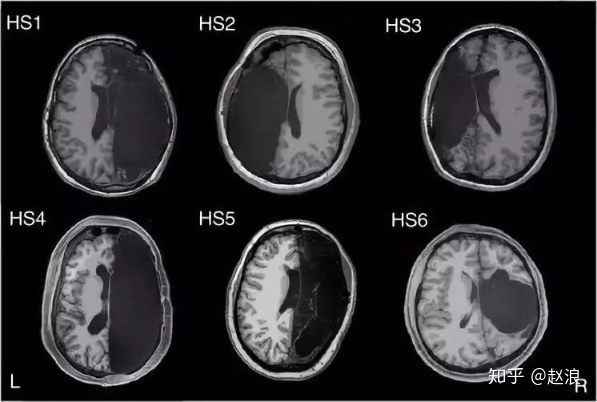

至于大脑,最多可以切掉一半。大脑半球切除术,目前依然是标准术式之一。虽然一般是病理性的大脑,但至少证明大脑切一半也行....